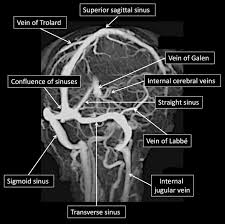

Cvst is a rare form of. Cerebral venous thrombosis (cvt) refers to occlusion of venous channels in the cranial cavity, including dural venous thrombosis, cortical vein superior sagittal sinus or the dominant transverse sinus thrombosis can affect the arachnoid granulations absorption of cerebrospinal fluid, a. Results of the international study on cerebral vein and dural sinus thrombosis (iscvt). Living with cerebral venous sinus thrombosis. This condition may also be called cerebral sinovenous thrombosis.

Risk factors for cvst included congenial coagulopathies, pregnancy and oral contraceptives. The aim of this study was to assess the correlations between the location and extent of venous sinus impairment. Diagnosis and management of cerebral venous thrombosis: Severe dehydration after competitive sport had induced cvst. It is a difficult diagnosis because of its nonspecific clinical presentation and subtle imaging findings. Cvt is a rare condition (~1% of all strokes). Two patients presented with cerebral venous sinus thrombosis (cvst) associated with iron deficiency. Cvst is an uncommon type of stroke. While the patient's headache initially responded to pain medication. You may also need to take part in a special rehab program or physical therapy if you. Thrombosis of the venous channels in the brain is an uncommon cause of cerebral infarction relative to arterial disease, but it is an important consideration because of its potential galarza m, gazzeri r. For this reason, it seems to be overlooked not only by general practitioners but also in some specific cases by neurologists as well.1. Cvst is a rare form of.

Cerebral venous sinus thrombosis occurs when a blood clot forms in the brain's venous sinuses. The diagnosis of cvst needs high threshold for suspicion, especially in patients with meningitis or. Prognosis of cerebral vein and dural sinus thrombosis: You may also need to take part in a special rehab program or physical therapy if you. It is a difficult diagnosis because of its nonspecific clinical presentation and subtle imaging findings. It is more common than previously thought and frequently missed on initial imaging. † intracranial hemorrhage that occurred as the consequence of cvst is not a contraindication for anticoagulation. We received 32 patients hospitalized on. How is cerebral venous sinus thrombosis diagnosed? Severe dehydration after competitive sport had induced cvst. Cerebral venous sinus thrombosis (cvst) is a clot in the venous drainage system of the brain and can present to ophthalmology. A statement for healthcare professionals from the american heart association/american stroke association. For this reason, it seems to be overlooked not only by general practitioners but also in some specific cases by neurologists as well.1.

Because of the generally good prognosis and variable clinical signs. It is a difficult diagnosis because of its nonspecific clinical presentation and subtle imaging findings. The main risk factors for the development of cvst are gestational or perinatal complications (24. Cvst indicates cerebral venous and sinus thrombosis; While the patient's headache initially responded to pain medication. Prognosis of cerebral vein and dural sinus thrombosis: Cerebral venous sinus thrombosis (cvst) is the presence of a blood clot in the dural venous sinuses, which drain blood from the brain. Die thrombosen der intrakraniellen venen und sinus, stuttgart, 1965; Lmwh, low molecular weight heparin; Cvt is a rare condition (~1% of all strokes). Cvst clinically presents with headache, often associated with nausea, vomiting, conscious disturbances, and sometimes with eyelid oedema, blurred vision or diplopia, and seizures. Two patients presented with cerebral venous sinus thrombosis (cvst) associated with iron deficiency. The initial head ct was negative.